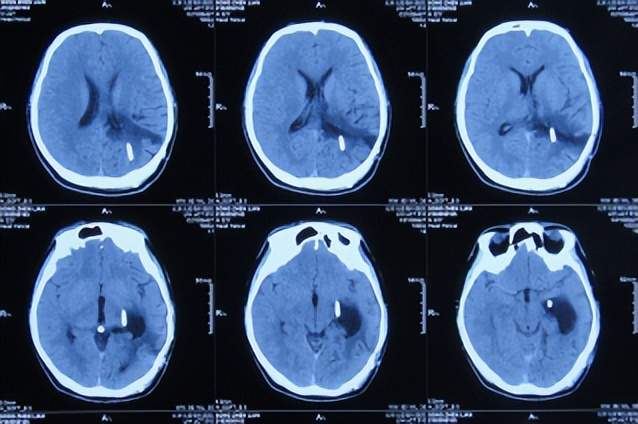

直到2021年1月8日(间断头痛4年后),因无法忍受头痛,就诊于山东省济南市商河某医院,查头颅核磁示颅内占位(图-1)。

图-1:2021年1月8日头颅核磁

为治疗脑瘤,于5天后即2021年1月13日,就诊于山东省某省级三甲医院,查头颅核磁增强(图-2)和头颅血管造影(图-3)示颅内占位。

图-2:2021年1月13日头颅核磁增强

入院后5天即2021年1月18日,查头颅CT增强示颅内占位(图-4)。

图-4:2021年1月18日头颅CT增强

入院后7天即2021年1月20日,进行了颅内占位切除术,留置引流管(图-5)。

图-5:2021年1月20日头颅CT

颅内占位切除术后次日即2021年1月21日,查头颅CT示脑瘤术后改变(图-6)。

图-6:2021年1月21日头颅CT

颅内占位切除术后第2天即2021年1月22日,头痛基本消失,脑瘤病理回报脑膜瘤;查头颅CT示脑室周水肿(图-7)。

图-7:2021年1月22日头颅CT

脑膜瘤术后第5天即2021年1月25日,查头颅是示水肿减轻(图-8)。

图-8:2021年1月25日头颅CT

术后第7天即2021年1月27日,拔除脑室外引流管(图-9),改行腰大池引流并给予抗感染治疗。

图-9:2021年1月27日头颅CT